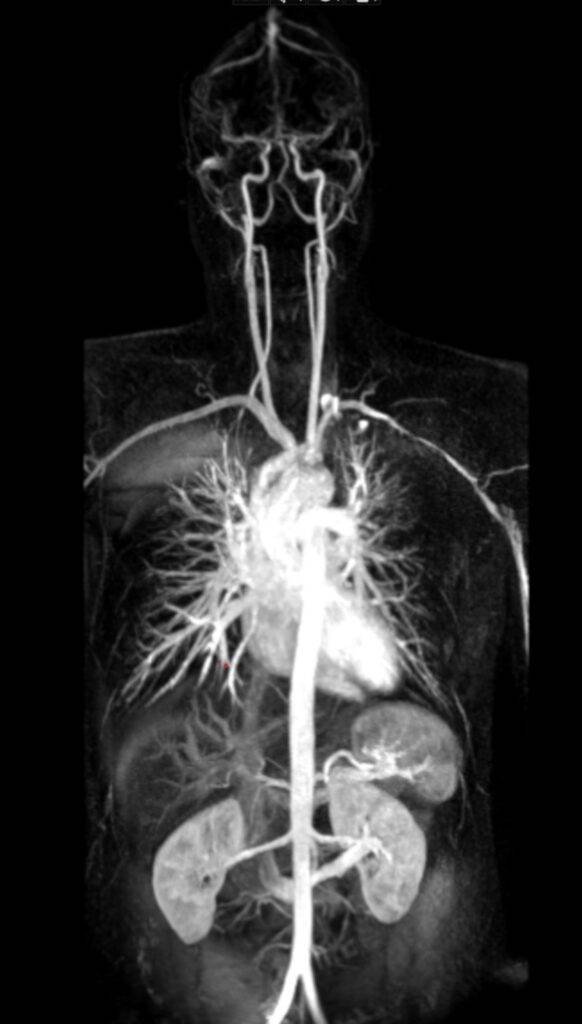

Eine Ganzkörper MRT ermöglicht es, unseren Körper – alle Organe, Gefäße, das Skelettsystem und die Gelenke, die wie Zahnräder ineinandergreifen und in ihrer Zusammenarbeit ein hochfunktionales System bilden – in seiner Ganzheit zu betrachten. Doch selbst in einem so ausgeklügelten System gibt es Schwachstellen die uns dazu veranlassen können, einen detaillierten Blick ins Körperinnere zu werfen.

Eine Ganzkörper MRT liefert hochauflösende Bilder des gesamten Körpers von Kopf bis Fuß und ist daher ideal für Vorsorgeuntersuchungen oder zur Verlaufsbeurteilung von malignen Erkrankungen:

- Eine Ganzkörper MRT kann in einer Untersuchung zur Abklärung komplexer Herz-Kreislauf-Erkrankungen herangezogen werden und gleichzeitig das gesamte Gefäßsystem sowie das Herz, die Lungen und die Bauchorgane dargestellten.

Die Ganzkörper-MRT stellt eine besonders detaillierte Methode in der medizinischen Bildgebung dar, die es ermöglicht, ohne die Verwendung ionisierender Strahlung, das Innenleben unseres Körpers umfassend zu visualisieren. Mittels starker Magnetfelder und Radiowellen wird der Körper in Gänze erfasst, wodurch ein vollständiges Bild der verschiedenen Organsysteme, der Gefäße sowie der Weichteile des Bewegungsapparates wie Muskeln, Sehnen und Gelenke ermöglicht wird.

Die Technologie erlaubt es, von Kopf bis Fuß ohne jegliche Strahlenbelastung detaillierte Einblicke in den menschlichen Körper zu erhalten und ist somit ideal für eine umfassende Gesundheitsüberprüfung und zur Früherkennung verschiedenster Erkrankungen geeignet. Die MRT Ganzkörper Untersuchung ist ein präzises und umfangreiches diagnostisches Bildgebungsverfahren.